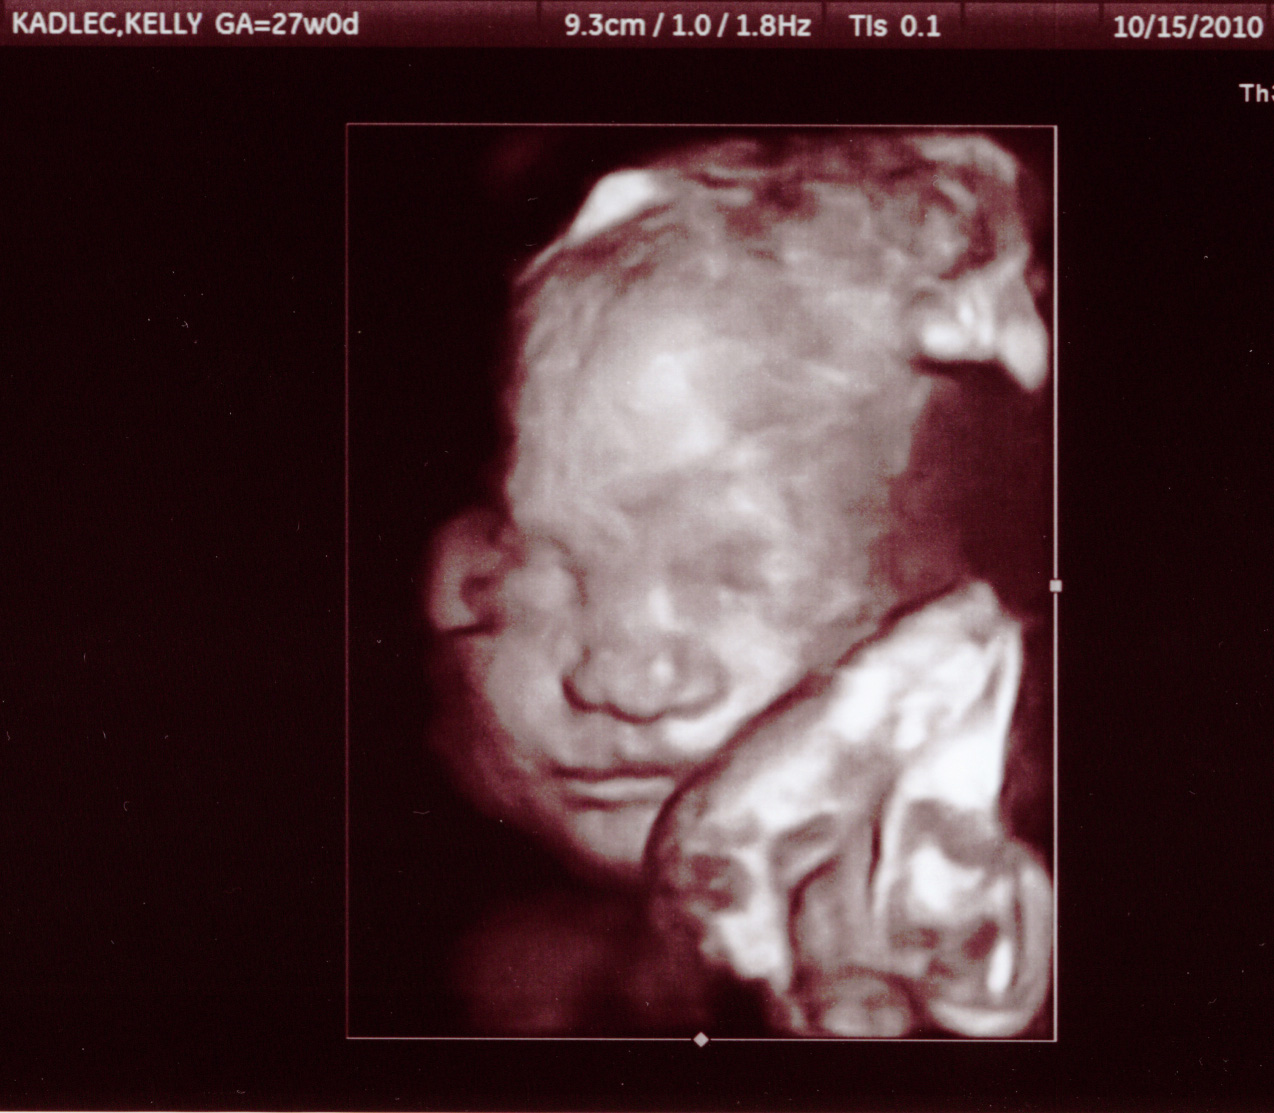

15 October 2010

Here are some pictures from our 27 week appointment.

He's a little over 2lbs.